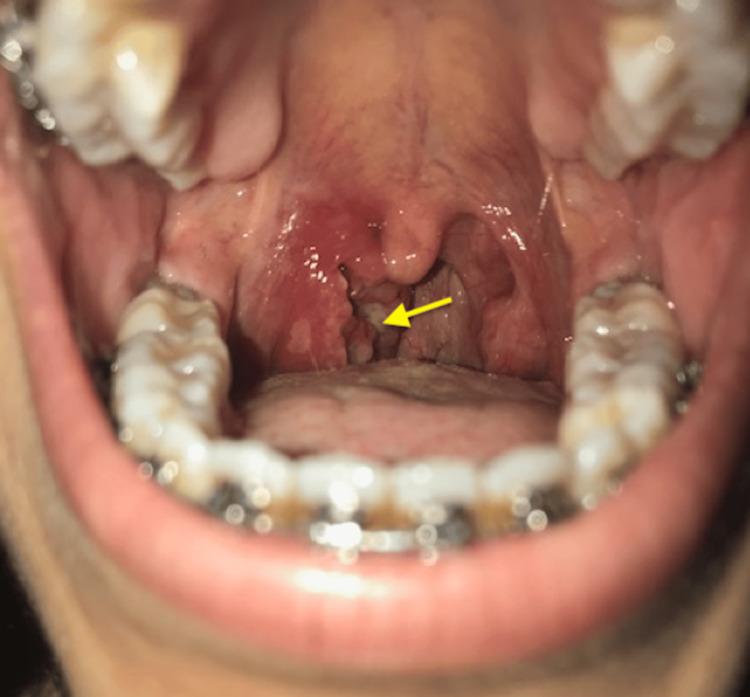

酷似癌症的扁桃体结核:一例报告

Tonsillar Tuberculosis Simulating Cancer: A Case Report.

Tuberculosis is still considered a cause of death, especially in developing countries. Primary tonsillar tuberculosis in the absence of pulmonary tuberculosis in an immunocompetent patient is a rare entity. Its diagnosis is difficult because it simulates tonsillar cancer, and histopathological examination is often needed for confirmation. We report the case of a 30-year-old woman with no history of tuberculosis and a normal lung CT. The lack of response to the initial treatment suggested either tumor pathology or germ-specific tonsillitis. The diagnosis of tonsillar tuberculosis was established based on the histological aspects provided by the tonsil biopsy and the QuantiFERON-TB test.

摘要

结核病仍然被认为是一种致死原因,尤其是在发展中国家。在免疫功能正常的患者中,原发性扁桃体结核而无肺结核是一种罕见的情况。其诊断困难,因为它类似扁桃体癌,通常需要组织病理学检查来确诊。我们报告一例30岁女性病例,该患者无结核病史且肺部CT正常。初始治疗无反应提示肿瘤性病变或特异性细菌引起的扁桃体炎。根据扁桃体活检提供的组织学特征和结核感染T细胞检测确诊为扁桃体结核。